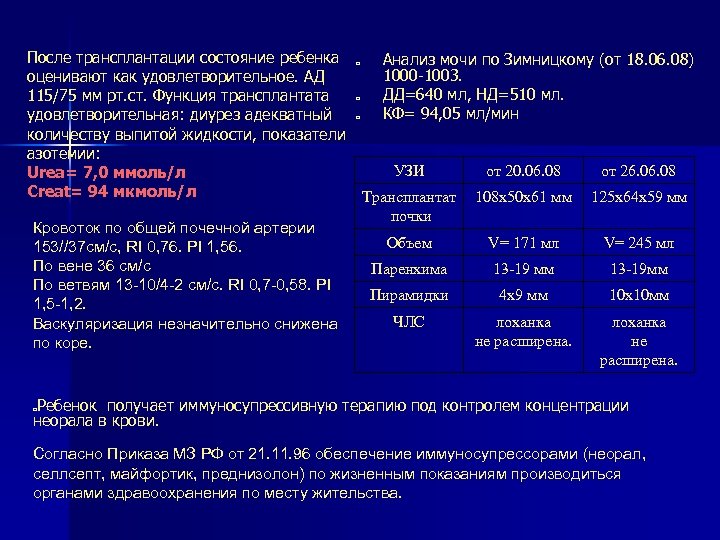

После трансплантации состояние ребенка оценивают как удовлетворительное. АД 115/75 мм рт. ст. Функция трансплантата удовлетворительная: диурез адекватный количеству выпитой жидкости, показатели азотемии: Urea= 7, 0 ммоль/л Creat= 94 мкмоль/л Кровоток по общей почечной артерии 153//37 см/с, RI 0, 76. PI 1, 56. По вене 36 см/с По ветвям 13 -10/4 -2 см/с. RI 0, 7 -0, 58. PI 1, 5 -1, 2. Васкуляризация незначительно снижена по коре. o o o Анализ мочи по Зимницкому (от 18. 06. 08) 1000 -1003. ДД=640 мл, НД=510 мл. КФ= 94, 05 мл/мин УЗИ от 20. 06. 08 от 26. 08 Трансплантат почки 108 х50 х61 мм 125 х64 х59 мм Объем V= 171 мл V= 245 мл Паренхима 13 -19 мм 13 -19 мм Пирамидки 4 х9 мм 10 х10 мм ЧЛС лоханка не расширена. Ребенок получает иммуносупрессивную терапию под контролем концентрации неорала в крови. o Согласно Приказа МЗ РФ от 21. 11. 96 обеспечение иммуносупрессорами (неорал, селлсепт, майфортик, преднизолон) по жизненным показаниям производиться органами здравоохранения по месту жительства.

После трансплантации состояние ребенка оценивают как удовлетворительное. АД 115/75 мм рт. ст. Функция трансплантата удовлетворительная: диурез адекватный количеству выпитой жидкости, показатели азотемии: Urea= 7, 0 ммоль/л Creat= 94 мкмоль/л Кровоток по общей почечной артерии 153//37 см/с, RI 0, 76. PI 1, 56. По вене 36 см/с По ветвям 13 -10/4 -2 см/с. RI 0, 7 -0, 58. PI 1, 5 -1, 2. Васкуляризация незначительно снижена по коре. o o o Анализ мочи по Зимницкому (от 18. 06. 08) 1000 -1003. ДД=640 мл, НД=510 мл. КФ= 94, 05 мл/мин УЗИ от 20. 06. 08 от 26. 08 Трансплантат почки 108 х50 х61 мм 125 х64 х59 мм Объем V= 171 мл V= 245 мл Паренхима 13 -19 мм 13 -19 мм Пирамидки 4 х9 мм 10 х10 мм ЧЛС лоханка не расширена. Ребенок получает иммуносупрессивную терапию под контролем концентрации неорала в крови. o Согласно Приказа МЗ РФ от 21. 11. 96 обеспечение иммуносупрессорами (неорал, селлсепт, майфортик, преднизолон) по жизненным показаниям производиться органами здравоохранения по месту жительства.